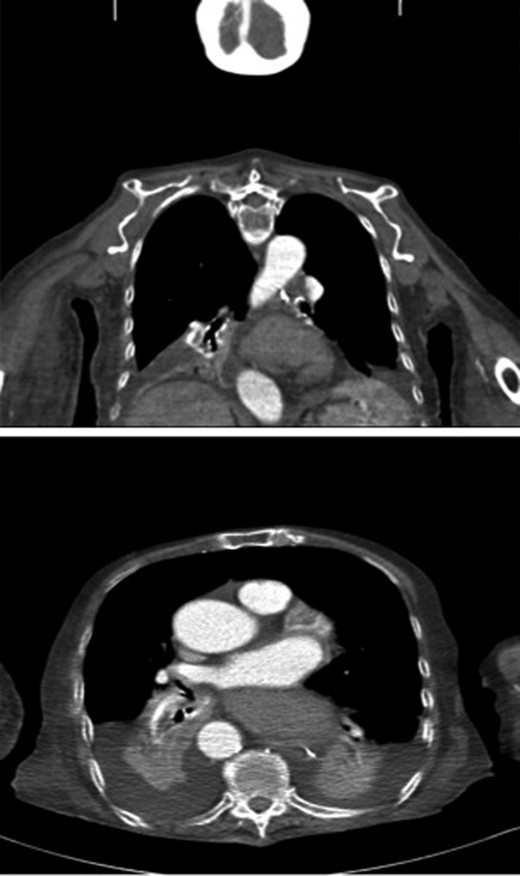

The patient was referred to ENT for endoscopic insertion of a nasogastric (NG) tube as the initial attempt failed. Resistance was noted at 40 cm and failure to pass beyond the lower oesophagus. Chest X-ray revealed the NG tube tip in the distal oesophagus (Fig. 2).

Chest X-ray showing the NG tube blocked at the distal oesophagus. The typical retrocardiac gas filled viscus cannot be seen.